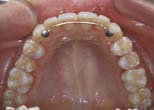

Ant. space closure or redistribution without movement of post. teeth